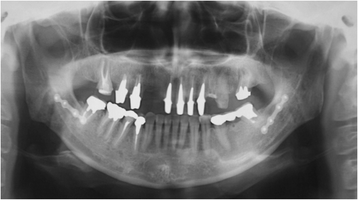

Many dental patients complain of oral symptoms after dental treatment, such as chronic pain or occlusal discomfort, for which the cause remains undetermined. These symptoms are often thought to be mental or emotional in origin, and patients are considered to have an "oral psychosomatic disorder". Representative medically unexplained oral symptoms/syndromes (MUOS) include burning mouth syndrome, atypical odontalgia, phantom bite syndrome, oral cenesthopathy, or halitophobia. With an increasing prevalence of these MUOS, dentists are being asked to develop new approaches to dental treatment, which include taking care of not only the patient's teeth but also the patient's suffering. Progress in the understanding of mind-body interactions will lead to investigations on the pathophysiology of MUOS and the development of new therapeutic approaches.